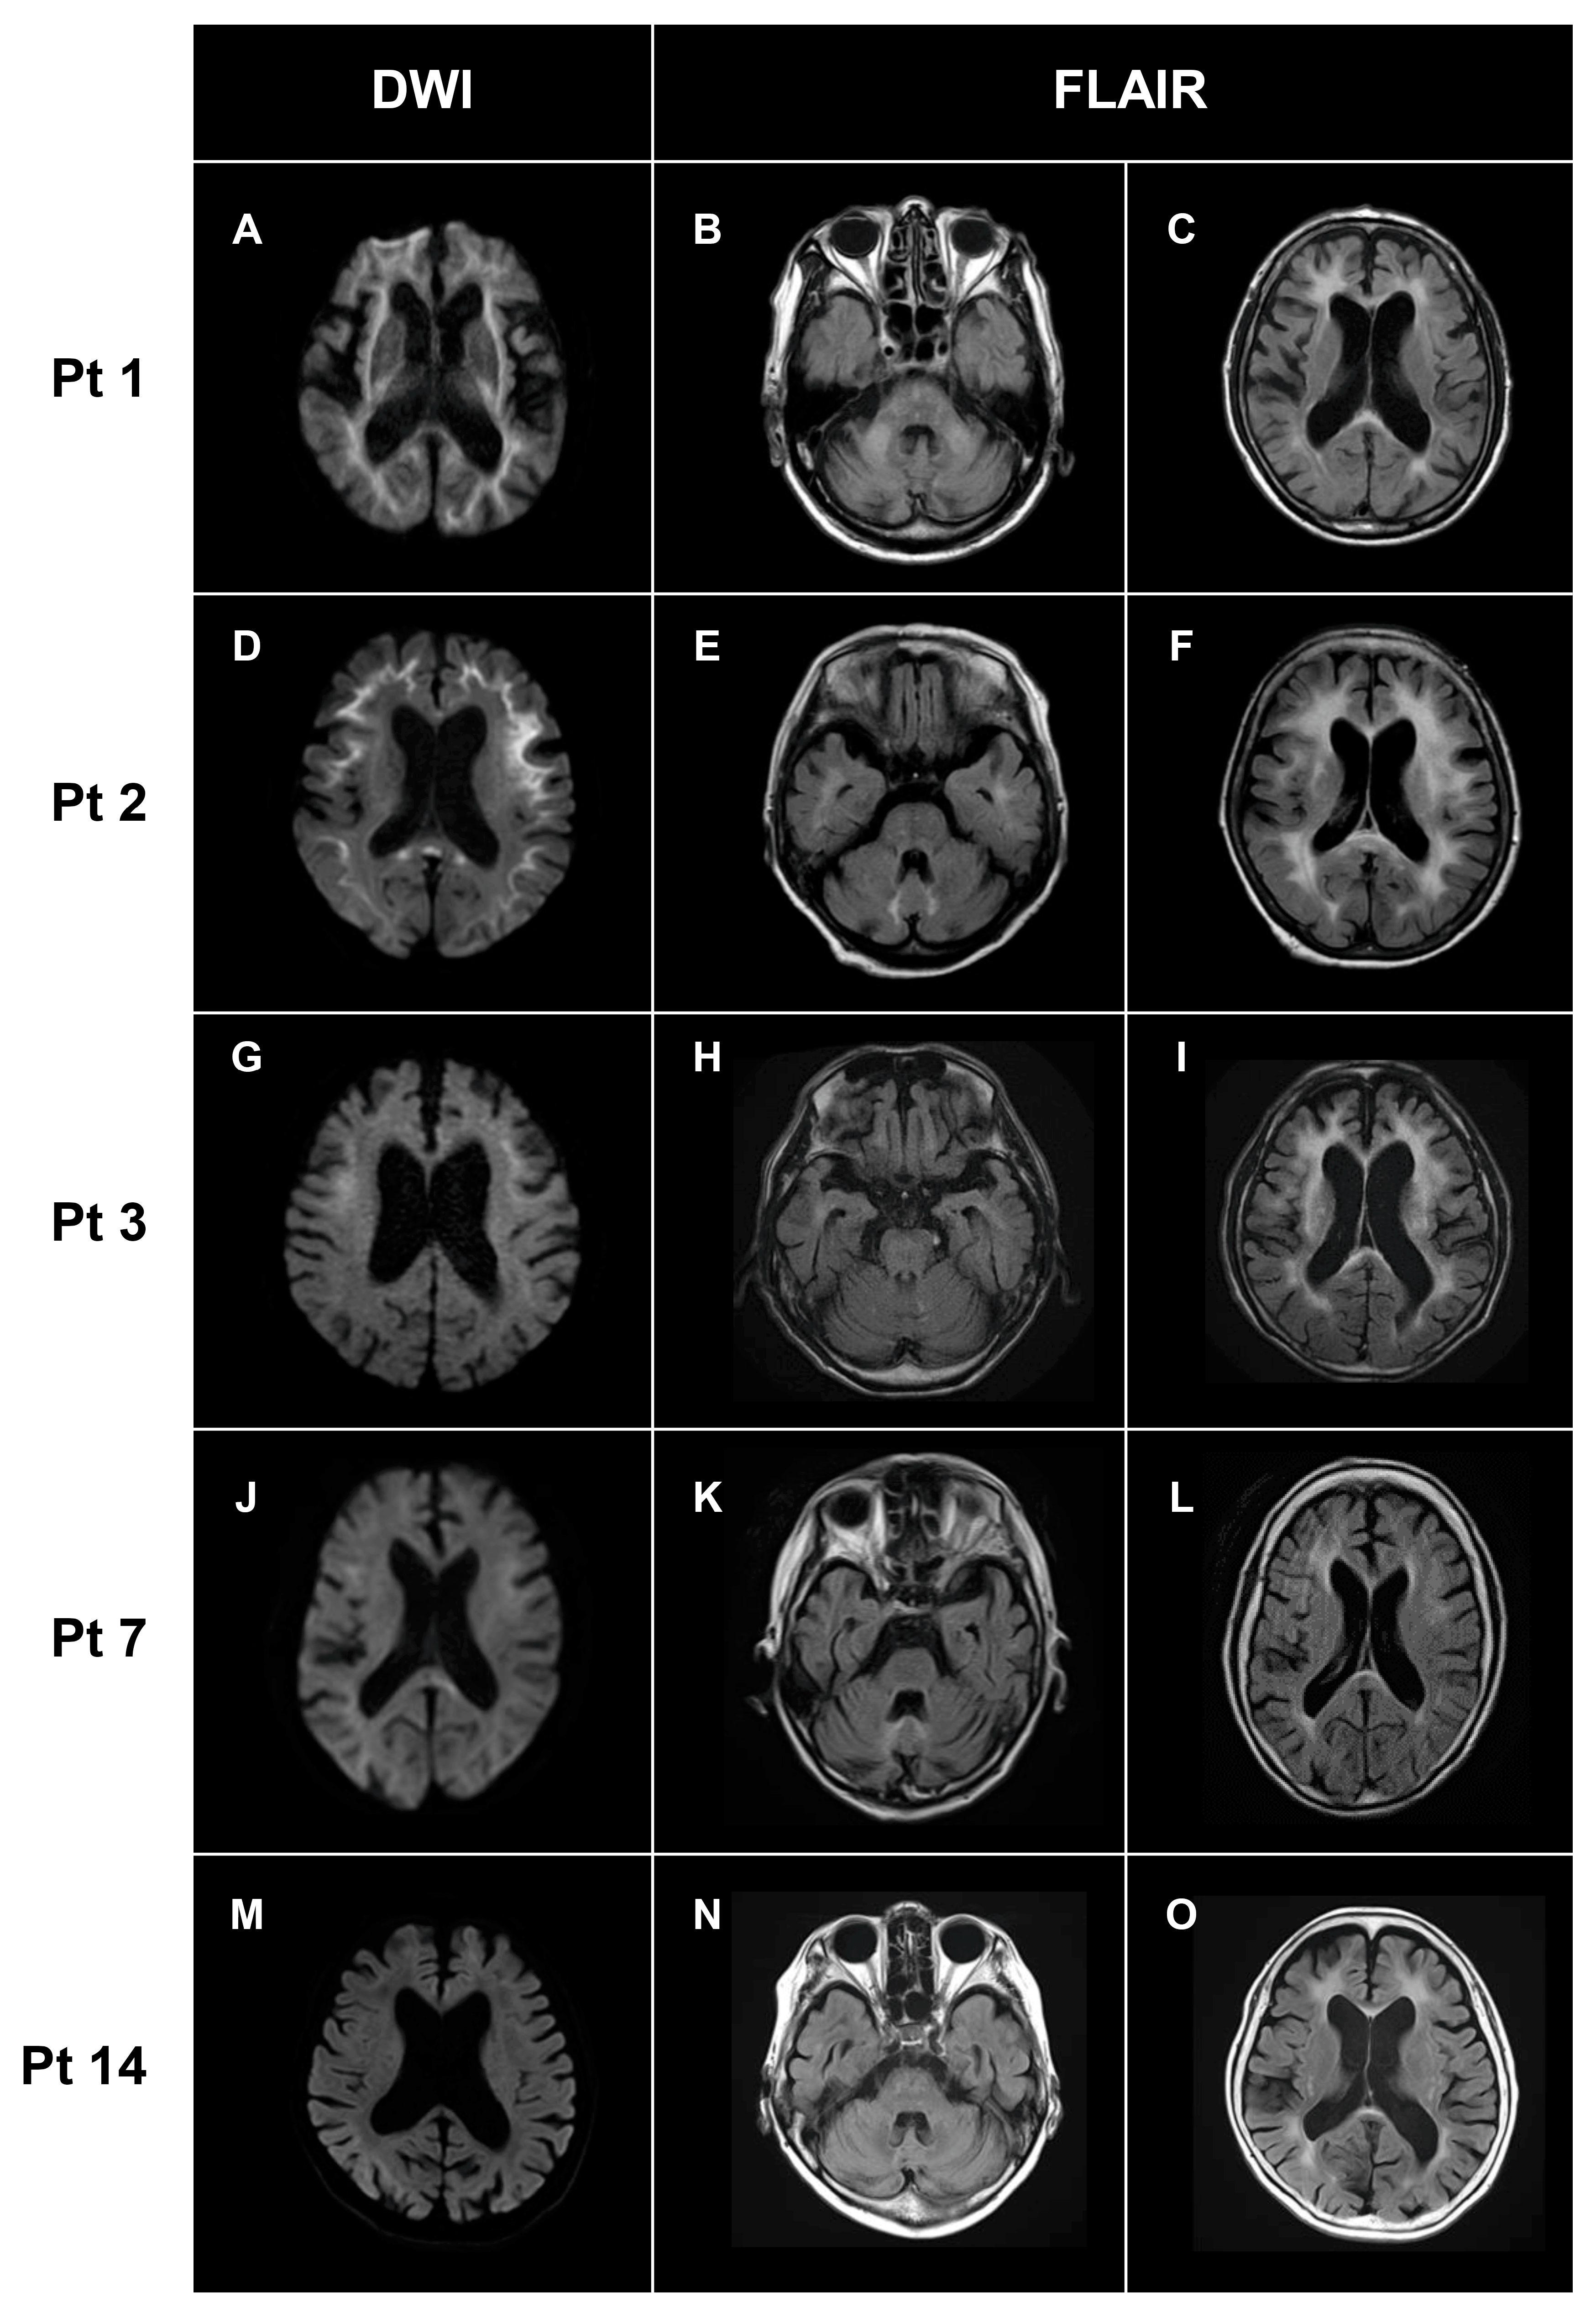

| White matter lesions | + | + | + | + | + | + | + | + | + | + | + | + | + | + | + | 15/15 (100%) |

| DWI high-intensity lesions in U-fibers | + | + | + | + | + | + | + | + | + | + | + | + | – | + | + | 14/15 (93%) |

| DWI high-intensity lesions in posterior lobe | + | – | + | – | + | – | + | – | + | – | + | + | – | – | - | 6/15 (44%) |

| DWI high-intensity lesions in corpus callosum | – | + | - | + | + | + | - | + | + | + | + | + | – | – | + | 10/15 (67%) |

| FLAIR high-intensity lesions in corpus callosum | + | + | + | + | + | - | - | + | + | + | + | – | – | – | + | 14/15 (93%) |

| Cerebellar atrophy | + | – | – | + | + | – | + | + | + | - | + | + | + | + | + | 11/15 (73%) |

| Middle cerebellar peduncle lesions | + | – | + | – | – | – | – | – | – | + | – | – | – | – | – | 3/15 (3%) |

| Paravermal lesions | – | + | – | – | + | – | + | + | – | – | – | + | – | – | + | 5/15 (33%) |